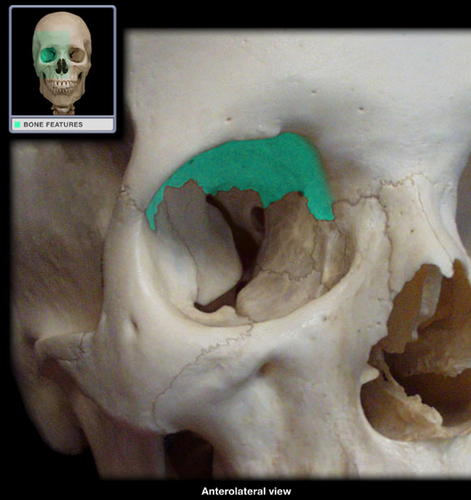

frontal

knowt flashcard image